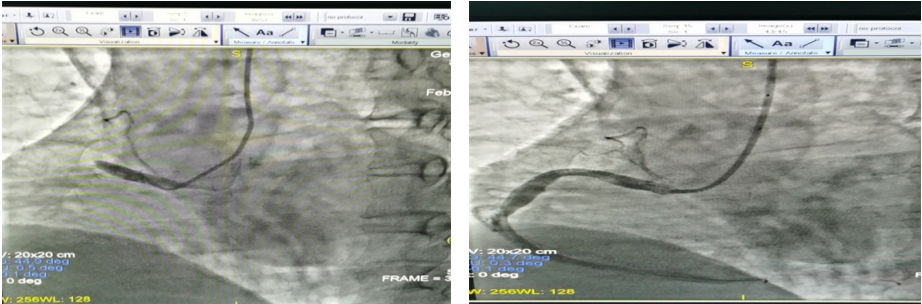

急性下壁心肌梗死术前 急性下壁心肌梗死治疗后